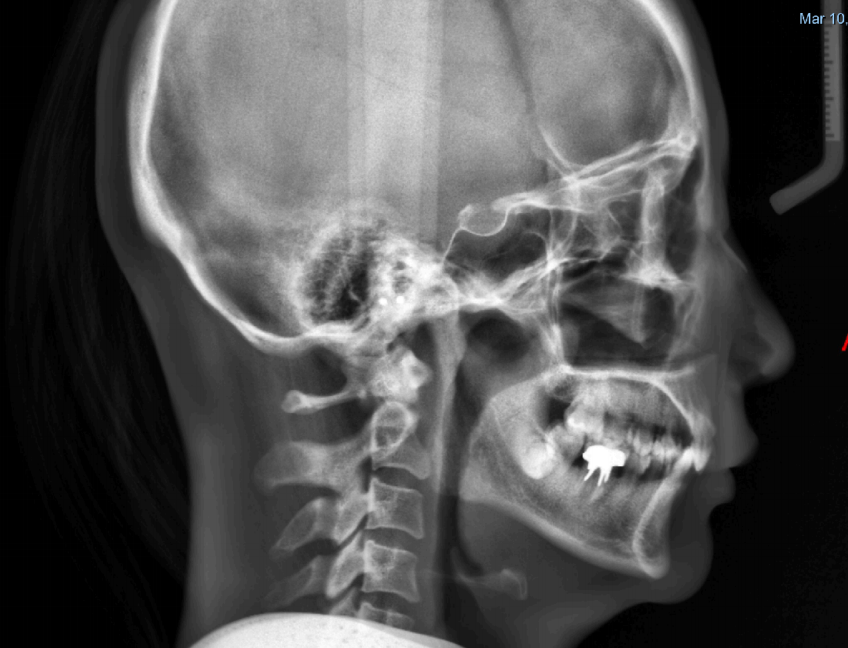

通过牙片资料可以看到女士是闭锁性深覆合,上牙几乎把下牙完全盖住,整个咬合关系并不是很理想,从侧貌看,她的下嘴唇相对靠后,下巴有点后缩,颏唇沟很深。

(1)不拔牙矫治,远中直立后牙,增加后部垂直高度,上颌少量扩弓,协调上下牙弓形态匹配,通过获取的牙弓间隙,排齐前牙,控根调整恢复上前牙正常转矩,矢状向不做过多内收。

(2)升高后牙,压低下前牙,实现升高后牙的前提是上下后牙之间有空间。因此上II类牵引引导下颌向前(牵引力量要缓和,以利于关节的改建),创造出后牙的颌间距离,也有利于隐形牙套升高后牙,由于女士露牙龈程度不大,所以适量压低前牙即可。